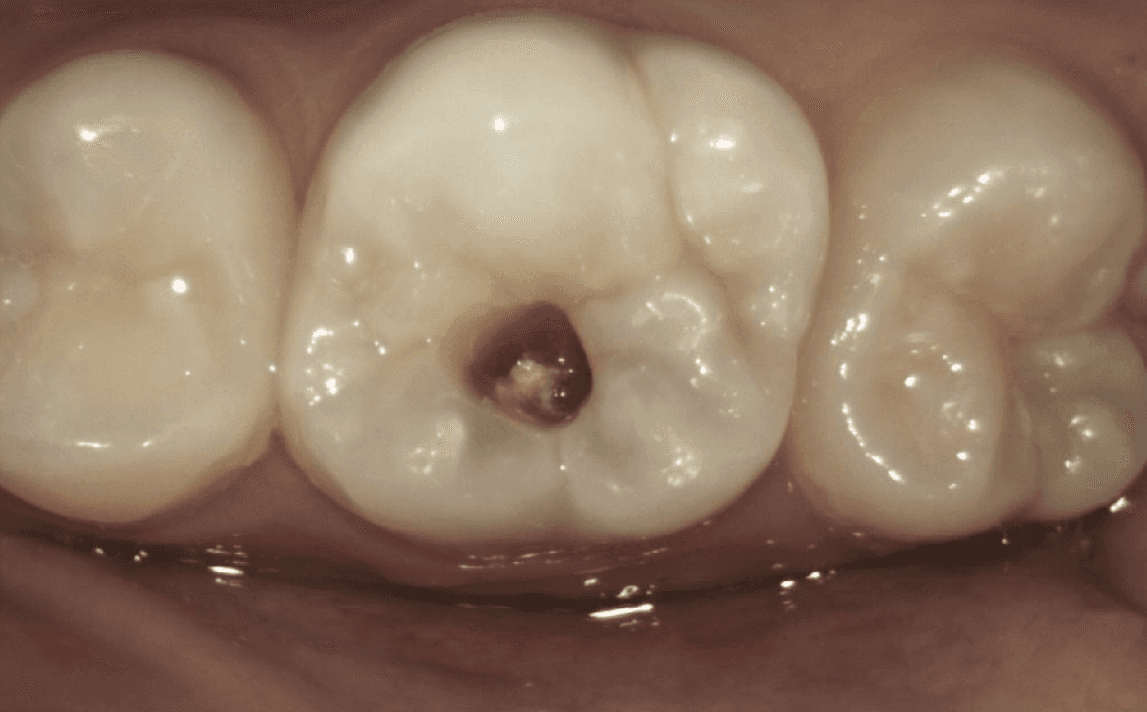

Take a look at the following example:

Greyness noted underneath the enamel, though the patient had no symptoms